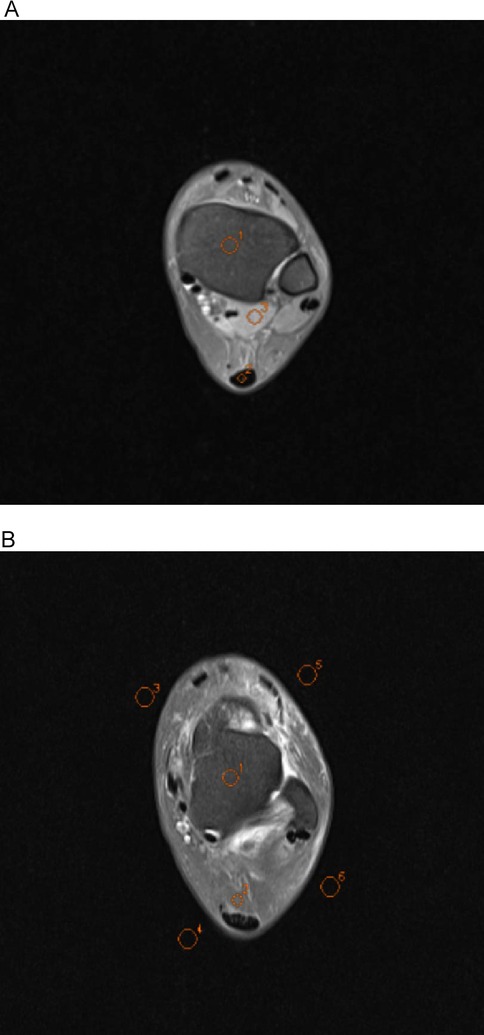

A senior radiographer (15 years of experience) performed quantitative measurements on a Siemens post-processing workstation under blinded conditions (no access to subject data or sequence parameters). Regions of interest (ROIs) were manually placed in the following anatomical structures on three consecutive slices at identical levels, window widths, and window positions: tibia (20–30 mm2), talus (20–30 mm2), Achilles tendon (5–10 mm2), Kager's fat pad (10–20 mm2) and flexor hallucis longus (20–30 mm2). The mean signal intensity (SI) of each ROI was calculated based on three consecutive measurements. Image background noise was quantified by placing four ROIs (40–50 mm2) in the artifact-free corners of the image, with the final noise level defined as the mean standard deviation (SD) of these regions (Figures 4A,B). The SNR and contrast-to-noise ratio (CNR) were calculated using the following formulas:

Figure 4

MRI scans of a cross-section of a limb, labeled A and B. In both images, various circular areas are highlighted with orange dotted lines, each numbered. The scans depict different tissue densities within the limb.

Figure 4. Axial ankle MR conventional raw images showing regions of interest (ROIs) used for quantitative analysis. All ROIs were manually delineated by a senior radiologic technologist (15 years of experience) under blinded conditions using the Siemens post-processing workstation. In image A, O1 indicates the tibia, O2 the Achilles tendon, and O3 the flexor hallucis longus; in image B, O1 represents the talus, O2 the Kager's fat pad, and O3–O6 the background regions for noise quantification.